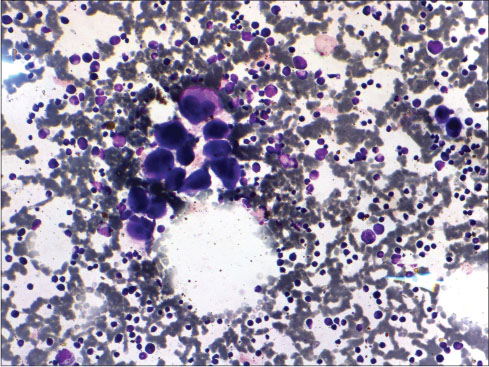

Her hemoglobin was 10 g/dl, white blood cell count was 11 × 109/L with predominance of neutrophils (75%), and platelet count was 20 × 109/L. No immature cells were observed in peripheral smear. Her lactate dehydrogenase was raised to 459 IU/L. Other serological tests including liver function, renal function, viral marker (Epstein–Barr virus [EBV], HIV, hepatitis B surface antigen, and hepatitis C virus) and autoimmune markers were unremarkable. Her prothrombin time, activated thromboplastin time was within the reference range. Fine-needle aspiration cytology (FNAC) smears from cervical lymph node showed a fair number of mononuclear Hodgkin cell and occasional binucleate and multinucleate Reed–Sternberg cell in a background of lymphocytes, plasma cells, neutrophils, and eosinophil. In view of FNAC findings, lymph node biopsy was done which confirmed HL of mixed cellularity type [Figure 1]. Staging work including imaging and bone marrow examination was done. Noncontrast computerized tomography scan of neck, thorax, and abdomen revealed multiple level II/III lymph nodes in the left cervical region largest measuring 5 cm × 2.5 cm. Also noted were hepatosplenomegaly along with multiple enlarged lymph nodes in perigastric, paracaval, aortocaval, and perisplenic region. Bone marrow examination did not show infiltration by Reed–Sternberg cells. In addition, the megakaryocytes were increased, in clusters, with predominance of early forms [compensatory response to thrombocytopenia, [Figure 2].[3] A final diagnosis of HL mixed cellularity stage III B bulky disease with ITP was made.

| Figure 2 CerBone marrow aspirate (Leishman stain × 200): Megakaryocyte cluster, with increased early forms